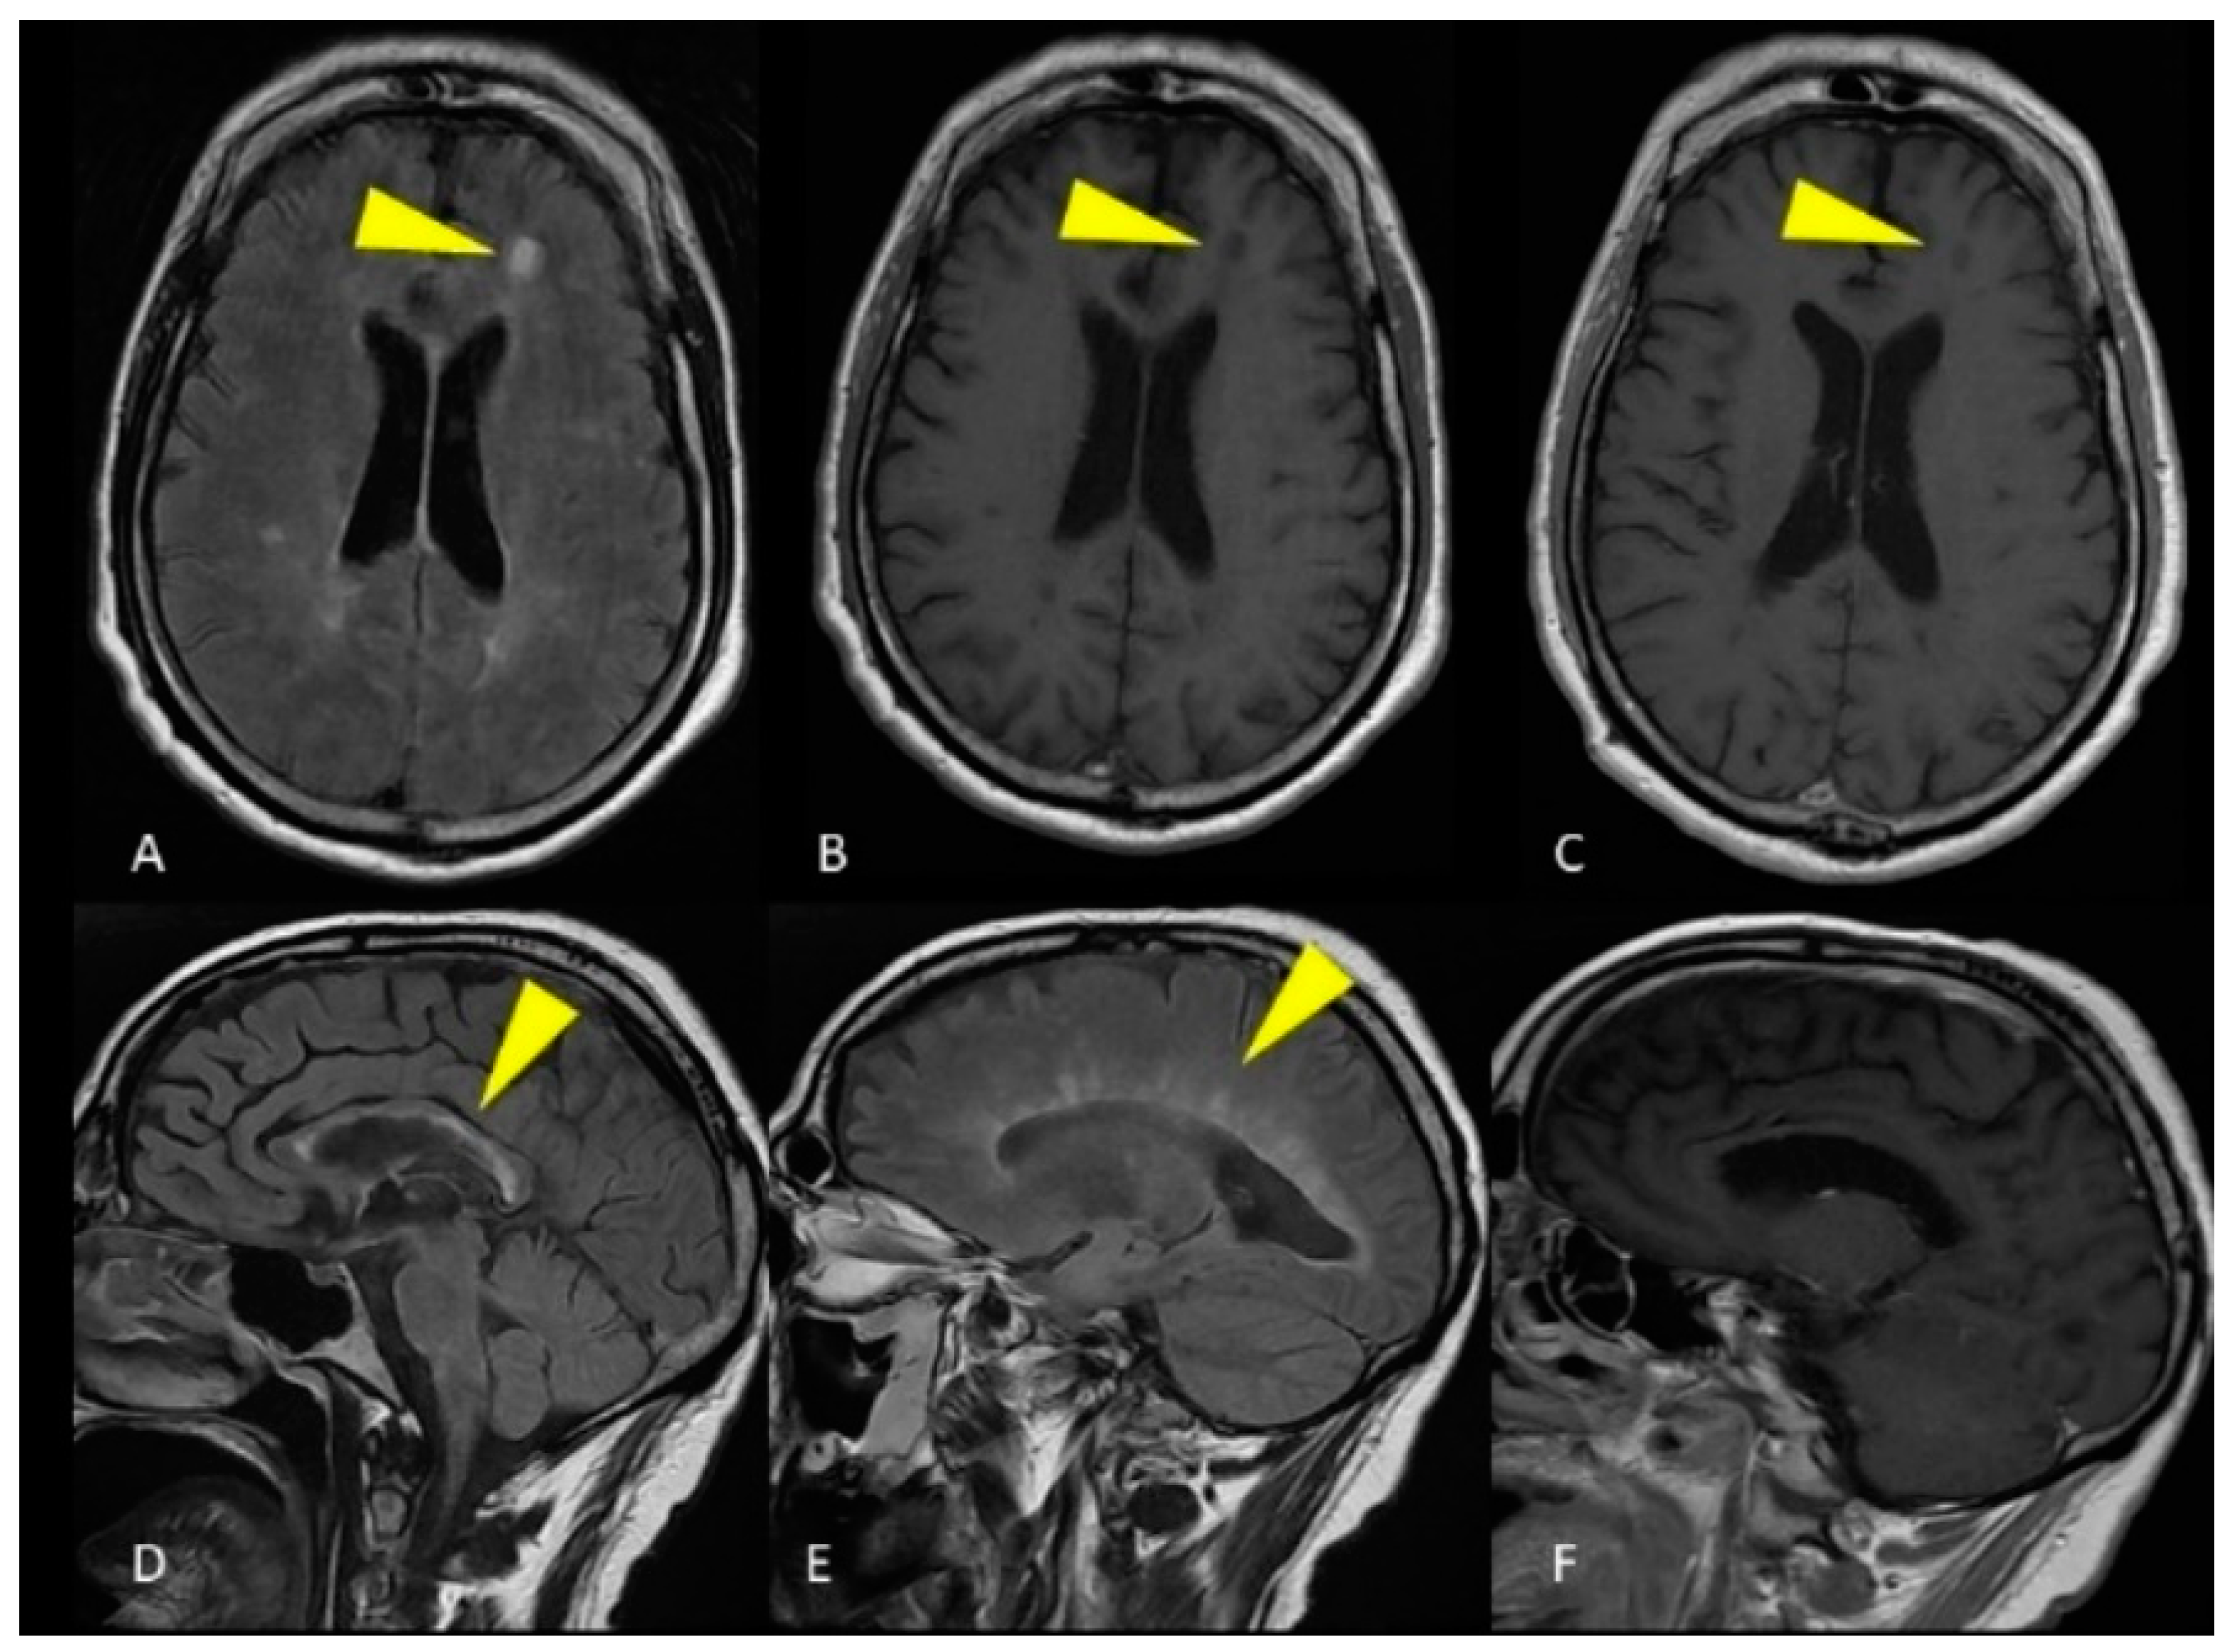

2.2. Case Presentation 2